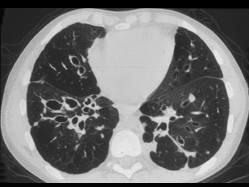

问题 男,18岁,咳嗽,咳痰,咯血半月余,CT检查如图,选出最可能的诊断 ( )

选项 A、大叶性肺炎 B、肺癌 C、支气管扩张 D、原发性肺结核 E、过敏性肺炎

答案 C